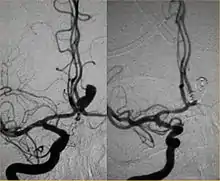

Intra-cranial angioplasty and stent of basilar artery stenosis